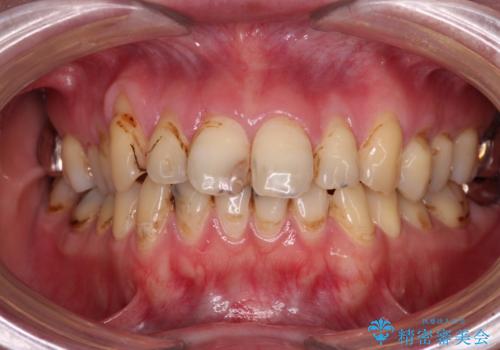

- 上下前歯や奥歯の虫歯治療を希望して来院された患者様です。

全顎的にむし歯が多く、根管治療の必要奥歯や、審美的に気になっている前歯を中心にオールセラミッククラウンにて補綴治療を行うこととしました。

上顎前歯は歯肉退縮により歯根が露出していたため、事前に歯肉移植術により根面被覆を行い、その後にオールセラミッククラウンを装着することとしました。